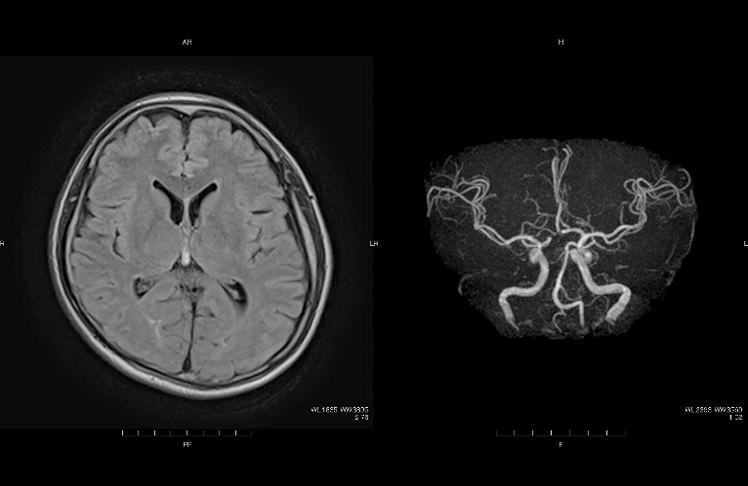

脳ドック

脳ドックでは、頭部のMRIとMRAおよび頚部MRAを主要な検査として行います。頭部MRIでは、隠れ脳梗塞や出血性病変などの脳血管障害の有無をはじめ、脳実質の萎縮の程度や腫瘍性病変の有無を調べることができます。MRAでは、脳動脈瘤の有無や脳動脈・頚動脈の狭窄の有無や狭窄の程度を把握できます。

オプションとしてタブレットで行う認知機能のスクリーニング検査やMRIによる萎縮度検査を行っています。

50歳以上の方には自覚症状はなくても一度は脳ドックを行っておくことをおすすめいたします。